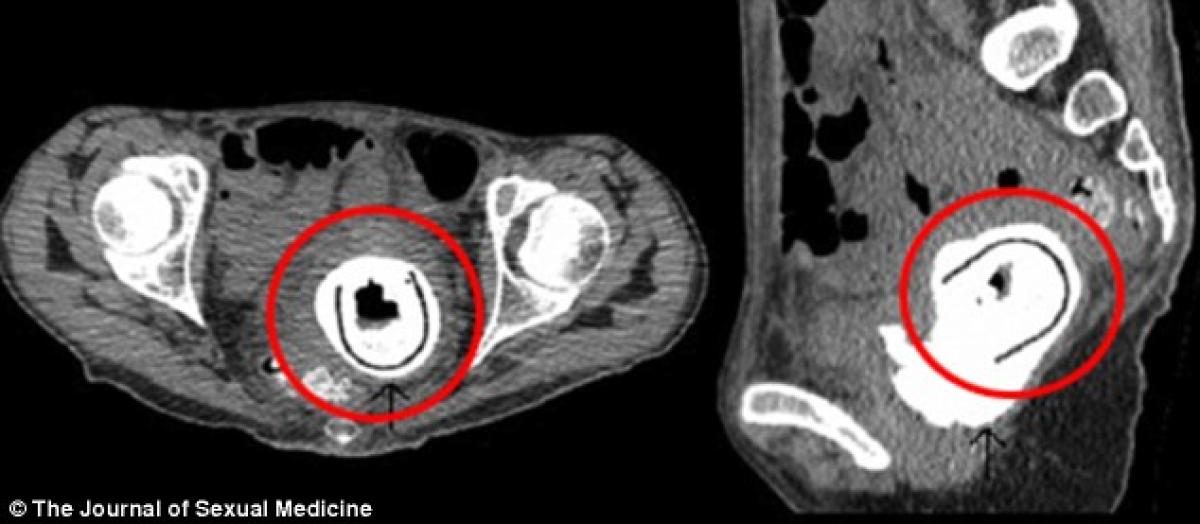

O femeie în vârstă de 38 de ani a ajuns la spital plângându-se de mari pierderi în greutate și letargie. Este vorba despre o doamnă din Scoția care a stat cu o jucărie sexuală de 12,7 cm în interior, timp de 10 ani.

Este vorba despre o doamnă din Scoția care a stat cu o jucărie sexuală de 12,7 cm în interior, timp de 10 ani.

La o examinare mai atentă însă, medicii au fost șocați să descopere un obiect straniu în vagin ce înțepa vezica.

Doctorii au fost cu atât mai uimiți cu cât pacienta a declarat că folosise jucăria în urmă cu 10 ani!

Jurnalul de Medicină Sexuală spune că este pentru prima oară când o asemenea jucărie este lăsată în interiorul unei femei preț de o decadă.